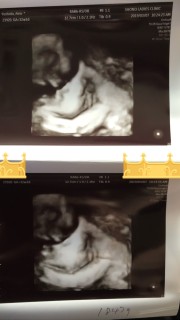

写真:32w1d:ケイトさん:こんなに開いたパー

なかなかお顔を見せてくれない息子ちゃん、今日のエコーでは手のひらを大きく開いてパーをして顔を隠していました(笑)先生もこんなに開いたパーをは珍しいね、と言ってくれました(^^)